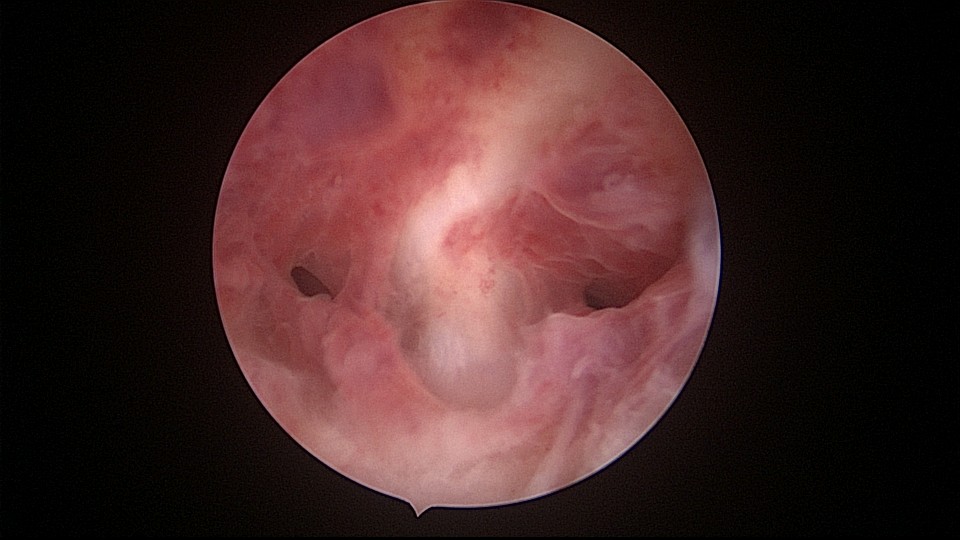

患者34岁,G4P1,顺产1次,继发不孕,宫腔容积小,宫腔粘连。2020年9月宫腔镜探查,见宫腔下段幕状粘连,两侧小孔与宫腔上段相通,形成假的输卵管开口。双极电针切开粘连,宫腔形态恢复正常,显露双侧输卵管正常开口。2020年10月宫腔镜二探取球囊,宫腔形态正常,双侧输卵管开口可见。2021年6月自然妊娠,2022年2月足月剖宫产分娩,2023年5月再次妊娠1次,人流终止妊娠。现39岁,G6P2,顺产1次,剖宫产1次。